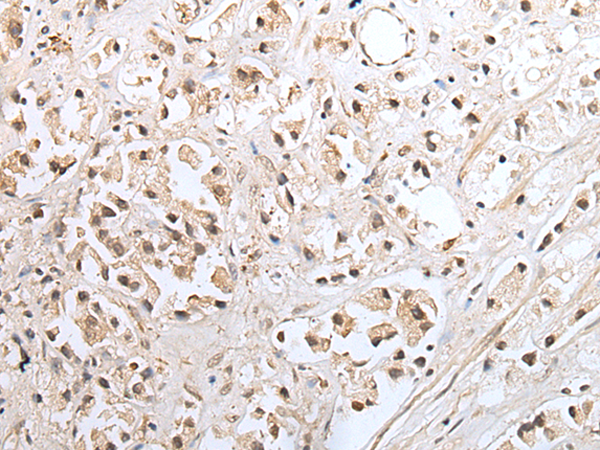

ELISA, IHC |

IHC positive control: |

Human gastric cancer and human prostate cancer |

IHC Recommend dilution: |

25-100 |